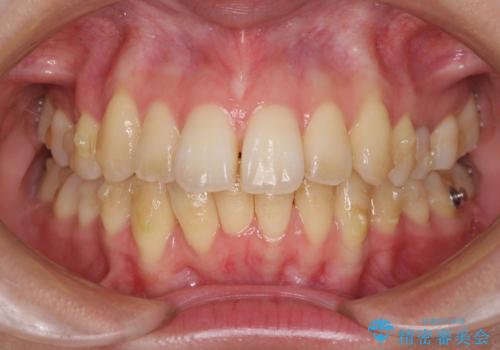

- 上の前歯、および下の歯列全体のでこぼこを気にして来院された患者様です。

インビザラインを用い、IPR(歯と歯の間を削る)と歯列全体を後方に移動させることで、歯並びを整えていくこととしました。

突出した印象のあった前歯をきれいに引っ込めることができたので、口が閉じやすくなり、横顔の印象をスッキリとさせることができました。

でこぼこしていて磨きにくかった歯と歯の間も清掃しやすくなり、患者様には大変満足していただきました。